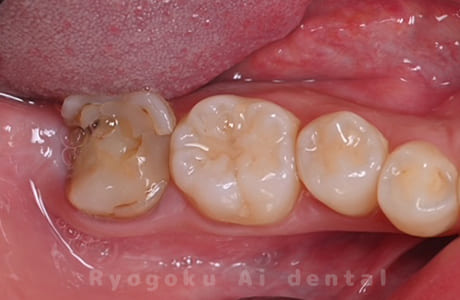

Case12

- 縁下カリエス

- 治療内容

- クラウンレングスニング、ジルコニアクラウン修復

- 治療費用

- 約220,000円

被せ物の中から臭いがするとのことで、被せ物を外したところ大きな虫歯となっていました。このまま被せてしまうと被せ物が外れやすいため、埋まっている歯を出すためのクラウンレングスニング処置を行い、その後、ジルコニアクラウンで被せ物を行いました。

<リスク・副作用>

手術後は痛み、腫れ、痺れ、青あざなどの副作用が生じます。痛みは痛み止めを処方しますが、腫れ、青あざは1週間程度生じる場合があります。また、部位によっては神経の走行が複雑で、痺れが残り、長期的にお薬を処方する場合があります。